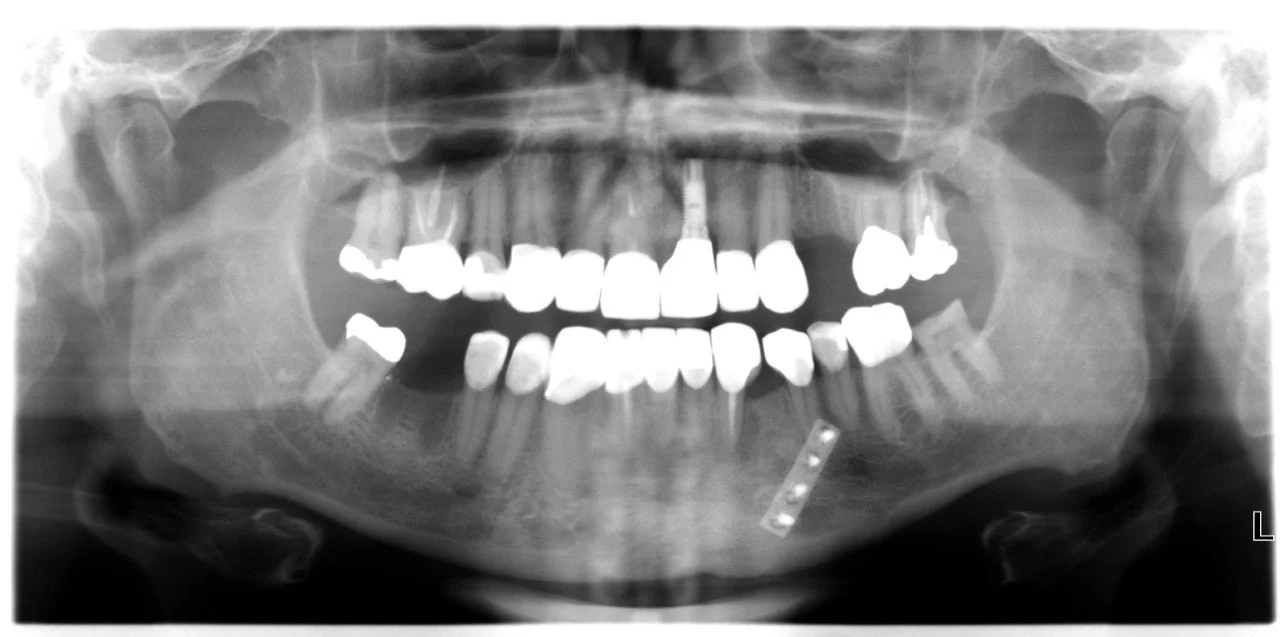

An OPG radiograph illustrating a variety of dental concerns and the presence of 2 implants in the lower jaw in the first premolar regions, namely, 34 and 44.

-

An OPG radiograph after the 6 extractions and Dr. Darveniza in 2014 surgically placed 2 Branemark implant fixtures between the existing 2 Ankylosis implant fixtures along with some artificial powdered RTR bone. Bone grafting adjacent to these Ankylosis implants was required following the extraction of the lower canines which had bone loss adjacent the 34 and 44 implant fixtures.